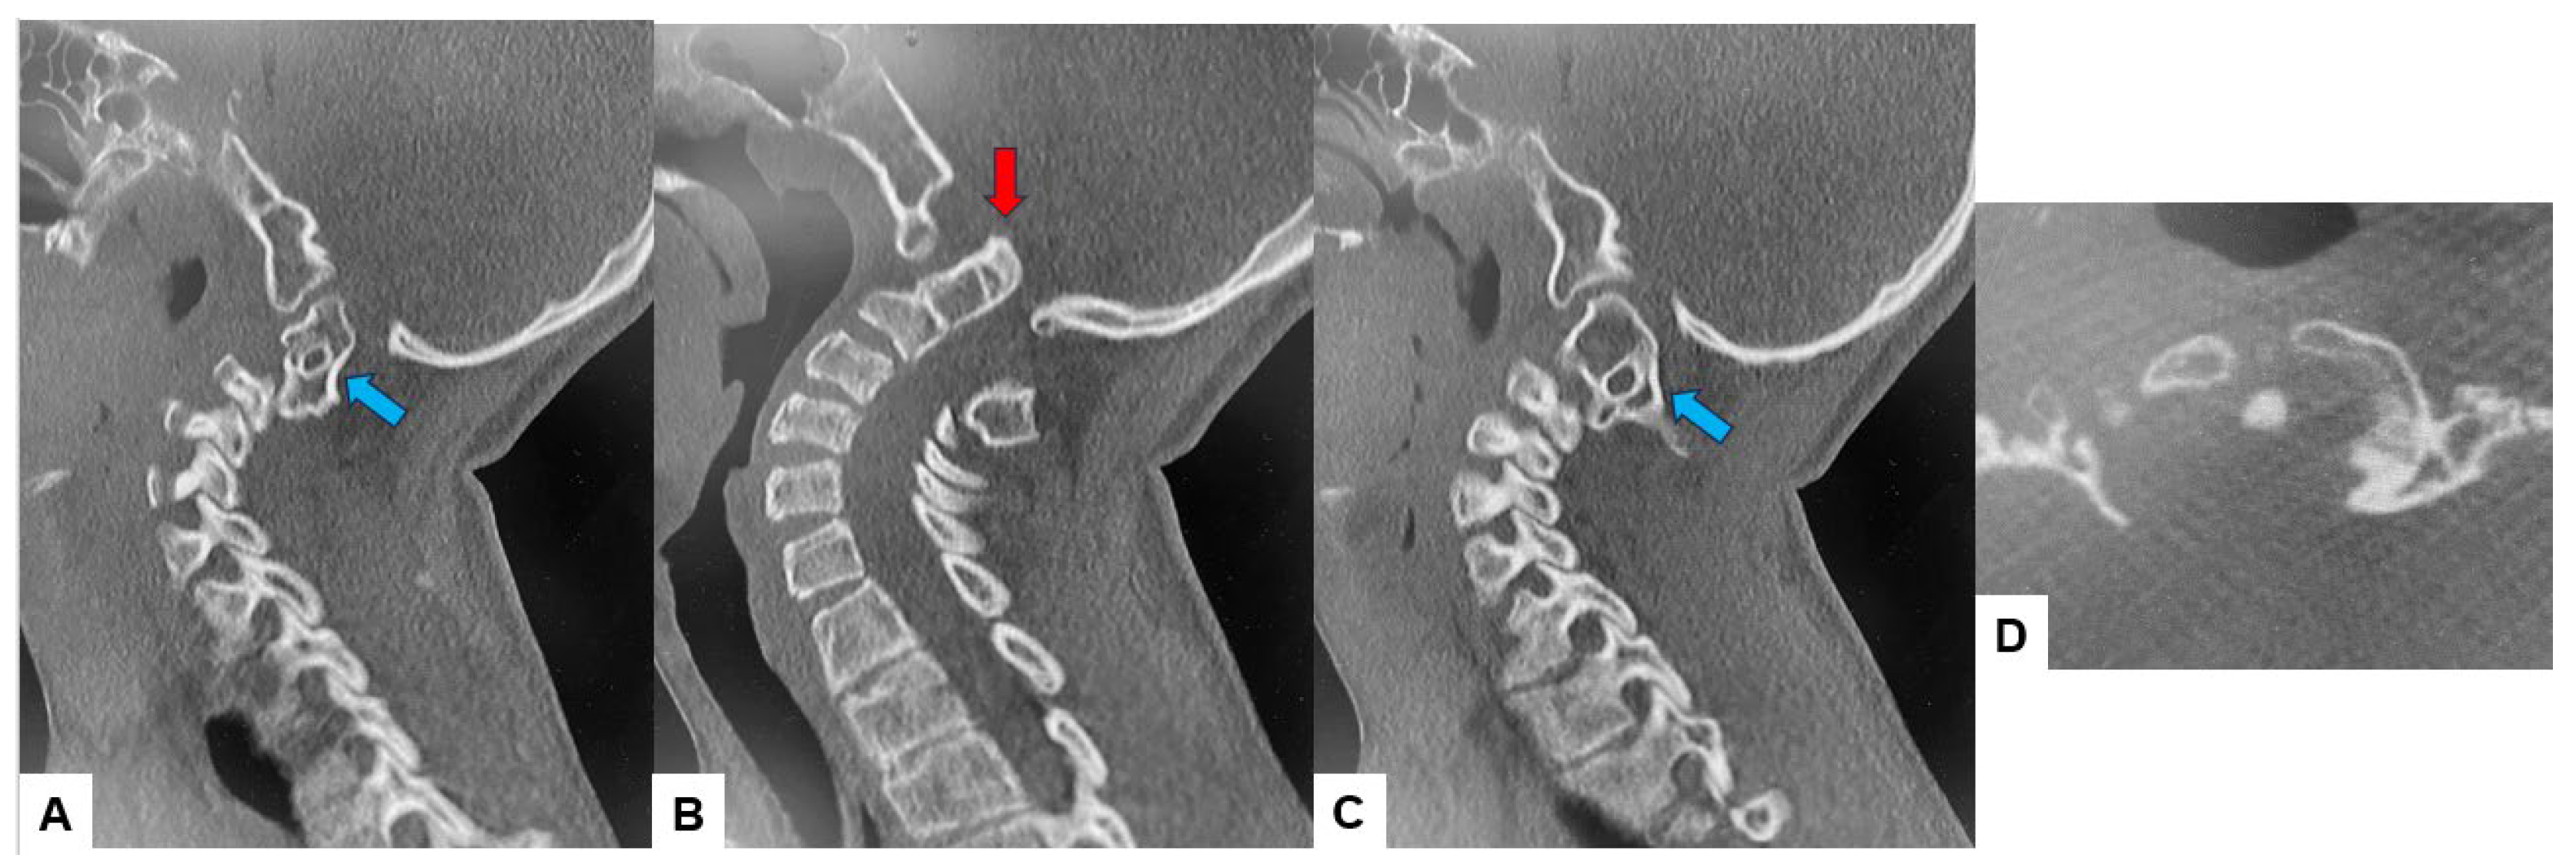

The CT scan clearly depicted the C2/3 fusion anomaly (Figure 4), while the 3D-CT scan revealed an abnormal course of the vertebral artery (Figure 5).

Figure 4.

Preoperative CT, (A) Right sagittal reconstruction CT, (B) Mid-sagittal reconstruction CT, (C) Right sagittal reconstruction CT, (D) Axial CT at C1/2. The odontoid process was protruded into the foramen magnum (red arrow). C2 and C3 were fused (blue arrow).